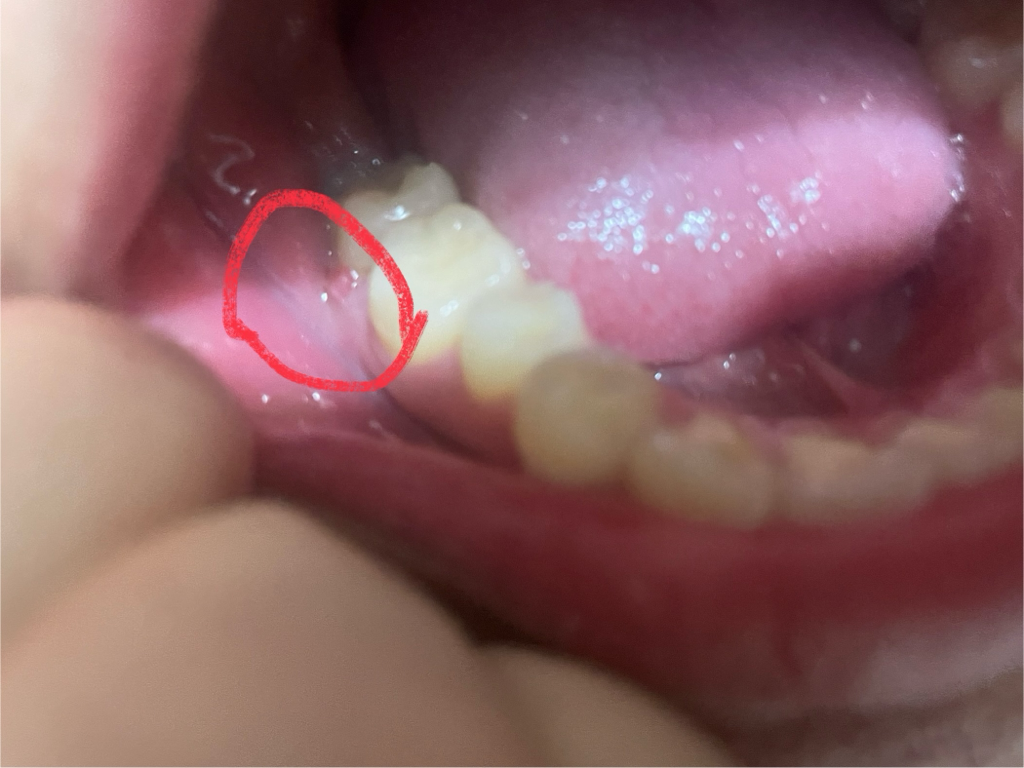

잇몸에 염증이 생겨서 그렇습니다. 많이 불편하시면 치과에 가셔서 잇몸치료를 하시는게 좋을것같습니다.

잇몸에 염증이 생기고 흔들리면 칫솔질이나 치실을 사용할 때 쉽게 출혈이 발생합니다.

잇몸에 염증이 있는 것으로 보이며, 붓기 및 통증 출혈이 반복되는 경우 치과에 방문하여 스케일링 및 잇몸 치료를 받길 권합니다.